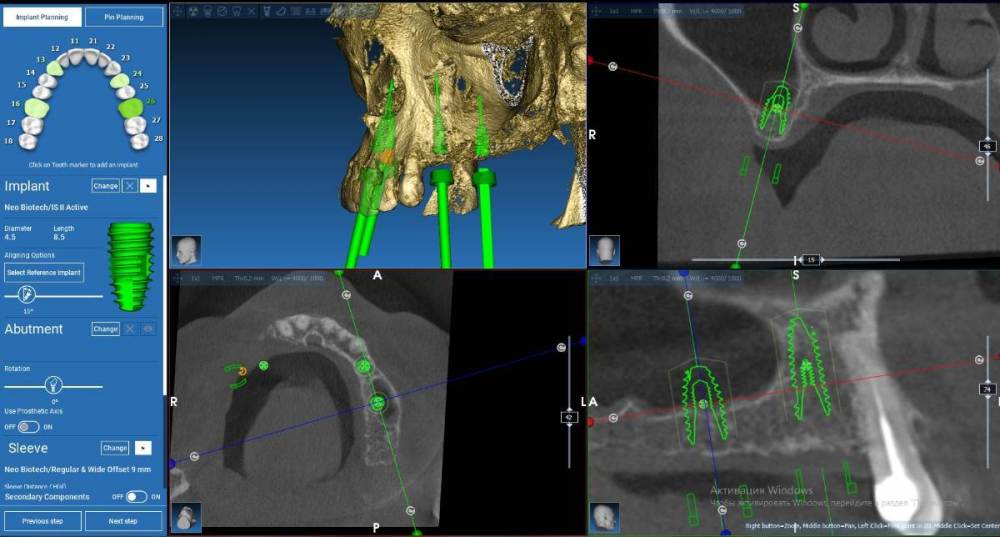

Fin Опубликовано 2 августа, 2022 Поделиться Опубликовано 2 августа, 2022 (изменено) Здравствуйте коллеги. Очень нужен ваш совет с планом лечения. Планирую установить 4 импланта на В.Ч.. В области зубов 2.4 и 2.6 все более менее понятно( 2.4 просто ставить а 2.6 ОСЛ и ставить), а вот в 1 сегменте все значительно сложнее. На данный момент имею три варианта конечно все варианты с навигационным шаблоном: 1.) 1.3 +НКР титановой сеткой (смущает что восстанавливать надо небно) 1.5 под углом и протезом на МЮ с небольшой консолью 1.6 (в виде премоляра) 2. 1.3 все так же либо рискнуть и оставить пару витков открытыми 1.5 имплант 4х10(11,5) и 1.7- 4х 7,3 с ЗСЛ 3 . Может Все таки пора начинать ставить анкилоз и поставить в обл 1.3 3,5х8 с небольшим оголением небной стенки.В остальный местах на этой стороне так же ануилоз. Протезрование делать с уровня МЮ. Благодарю Вас за советы. Скрины 2 сегмента Изменено 2 августа, 2022 пользователем Fin Ссылка на комментарий

АнтонТЛТ Опубликовано 2 августа, 2022 Поделиться Опубликовано 2 августа, 2022 @Fin сделайте расстановку зубов, исходите из положения ортопедического, а не условий костной ткани 2 Ссылка на комментарий

Fin Опубликовано 2 августа, 2022 Автор Поделиться Опубликовано 2 августа, 2022 (изменено) 1 час назад, АнтонТЛТ сказал: @Fin сделайте расстановку зубов, исходите из положения ортопедического, а не условий костной ткани Вы правы...Быстро сделал виртуально постановку, нужно наращивать с обеих сторон получается Изменено 2 августа, 2022 пользователем Fin Ссылка на комментарий

АнтонТЛТ Опубликовано 2 августа, 2022 Поделиться Опубликовано 2 августа, 2022 А теперь коронку по торку наклоните, чтобы рвущий бугор клыка был на одной дуге с режущим краем 12 и вестибулярного бугра 14 Ссылка на комментарий

Irouil Опубликовано 2 августа, 2022 Поделиться Опубликовано 2 августа, 2022 (изменено) Во первых я бы взял винт 3.6 Во вторых на этом скрине вроде бы нужно как раз небнее, так выход практически в бугор В третьих исходя из первых двух пунктов + конденсация вестибулярно все должно быть нормально В четвертых пятёрку бы дистальнее P.S. да, насчёт бугра Антон прав, он завален Вообще, все эти расстановки без макетирования на моделях меня немного смущают всегда Изменено 2 августа, 2022 пользователем Irouil 1 1 Ссылка на комментарий